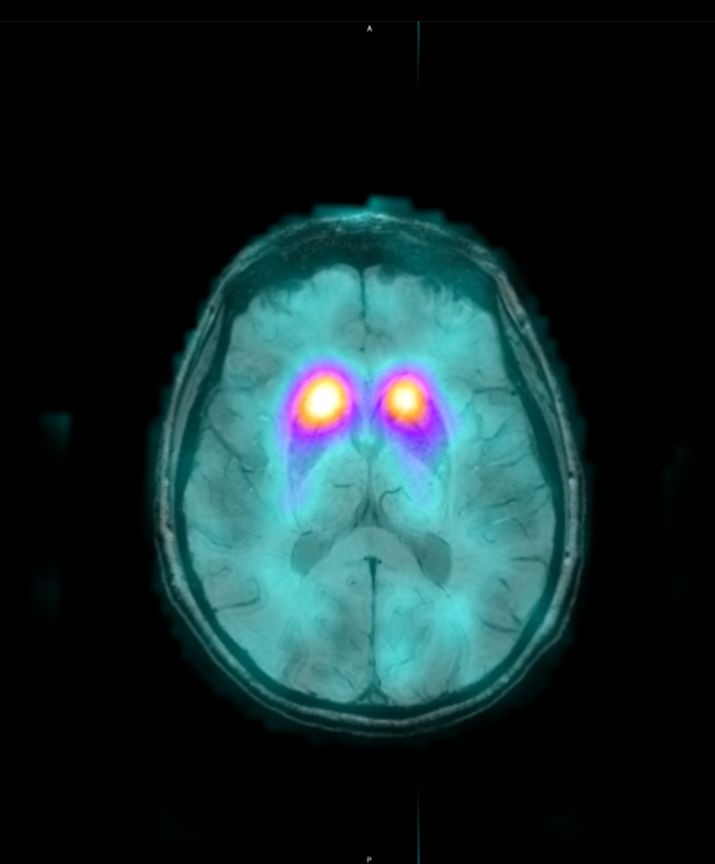

Το Lu-177 PSMA αποτελεί μια στοχευμένη ραδιονουκλιδική θεραπεία για ασθενείς με ορμονοάντοχο μεταστατικό καρκίνο του προστάτη (mCRPC), αξιοποιώντας τη υπερέκφραση του PSMA (Prostate-Specific Membrane Antigen) στα καρκινικά κύτταρα. Προηγείται PSMA PET/CT για ακριβή χαρτογράφηση της νόσου και επιβεβαίωση επαρκούς πρόσληψης του ραδιοφάρμακου. Το Lu-177 PSMA συνδέεται στους PSMA-υποδοχείς, επιτρέποντας στοχευμένη ακτινική δράση υψηλής κυτταροτοξικότητας σε μεταστατικές εστίες οστών και μαλακών μορίων. Η χρήση εξειδικευμένων δοσιμετρικών εργαλείων επιτρέπει την ποσοτική αποτίμηση της δόσης σε κρίσιμα όργανα (π.χ. σιελογόνοι αδένες, νεφροί, μυελός) και στον όγκο, συμβάλλοντας σε εξατομικευμένη θεραπευτική προσέγγιση. Μετά από κάθε κύκλο πραγματοποιείται PSMA PET/CT ή FDG PET/CT (όπου ενδείκνυται), καθώς και στενός αιματολογικός έλεγχος για αξιολόγηση της ανταπόκρισης και των πιθανών τοξικοτήτων. Η θεραπεία έχει αποδειχθεί ιδιαίτερα αποτελεσματική στη μείωση του καρκινικού φορτίου, στη βελτίωση του πόνου, στη μείωση των επιπέδων PSA και στη σημαντική παράταση του προσδόκιμου επιβίωσης σε ασθενείς με εκτεταμένη και ανθεκτική νόσο.

Συνδυάζουμε στοχευμένα ραδιοφάρμακα που απεικονίζουν και θεραπεύουν τον ίδιο μοριακό στόχο. Στο ΥΓΕΙΑ το πρόγραμμα αφορά:

Με τη SPECT‑CT ποσοτικοποίηση υπολογίζουμε απορροφούμενες δόσεις σε όγκους και όργανα‑στόχους (νεφροί, σιελογόνοι, ήπαρ, μυελός κ.ά.). Αυτό: